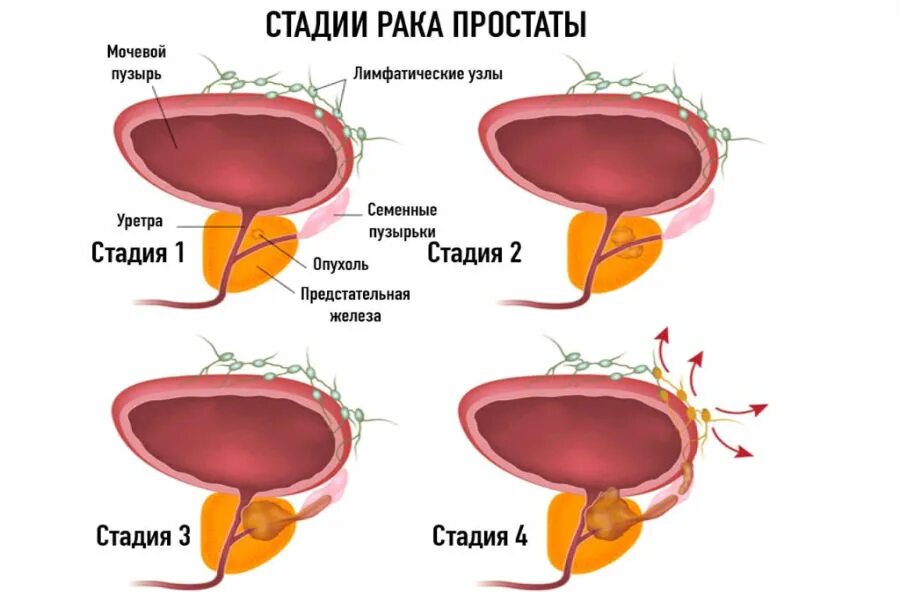

Предстательная железа фото Онкология предстательной железы. Степени опухолей простаты. Предстательная железа rak. Стадии опухоли простаты

Онкология предстательной железы. Степени опухолей простаты. Предстательная железа rak. Стадии опухоли простаты

Анатомия аденомы предстательной железы. Эктопия предстательной железы. Злокачественная опухоль предстательной железы. Злокачественная аденома предстательной железы Карцинома 4 степени предстательной железы. Онкология предстательной железы. Опухоль предстательной железы стадии

Карцинома 4 степени предстательной железы. Онкология предстательной железы. Опухоль предстательной железы стадии Эластография предстательной железы. Компрессионная эластография предстательной железы. УЗИ С эластографией предстательной железы. Образование предстательной железы УЗИ

Злокачественная опухоль предстательной железы. Злокачественные новообразования простаты. Карцинома предстательной железы. Стадии опухоли простаты Опухоль предстательной железы стадии. Стадии онкологии предстательной железы. Стадии аденомы предстательной железы

Опухоль предстательной железы стадии. Стадии онкологии предстательной железы. Стадии аденомы предстательной железы